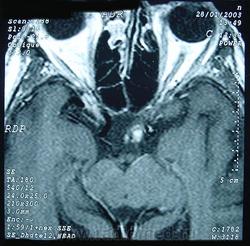

ГМ. Кавернома 2. Кавернома зрительного тракта. +

Кавернома зрительного тракта

Отдел патологии, школа медицинских наук. Государственного Университета Кампинас (UNICAMP). Кампинас, Сан-Паулу, Бразилия.